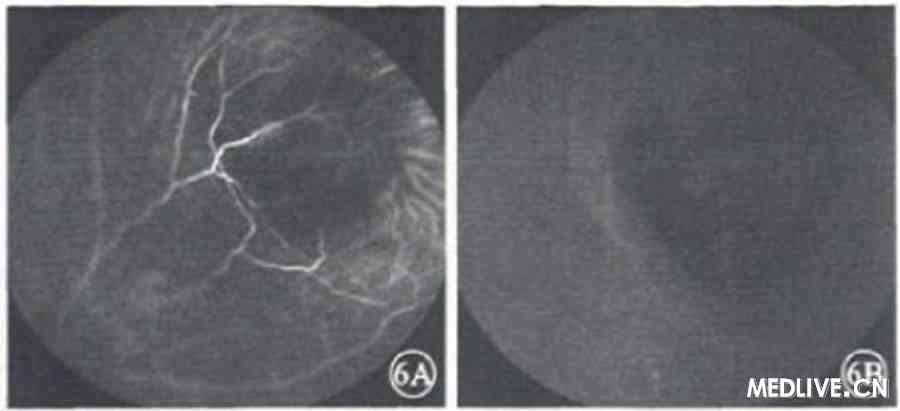

吲哚青绿血管造影(ICGA)检查,早晚期右眼病灶区呈持续弱荧光(图6)。

图5右眼FFA检查像。5A.早期可见病灶表面视网膜血管扩张,荧光渗漏;5B.晚期可见病灶局部视网膜染色 图6 右眼ICGA检查像。6A.早期.6B.晚期;病灶区持续弱荧光

图6 右眼ICGA检查像。6A.早期.6B.晚期;病灶区持续弱荧光

本例患者眼底病灶位于鼻上方周边视网膜下;FFA早期病灶表面视网膜毛细血管明显扩张,轻度荧光渗漏,晚期病灶局部荧光着染;ICGA早晚期病灶区呈持续弱荧光。其检查表现不同于脉络膜转移癌,全身检查也未见原发肿瘤,可排除脉络膜转移癌的诊断。

本例患者无结核病史及眼外结核表现,痰结核菌检查及PPD试验阴性。糖皮质激素治疗有效等特点均不支持脉络膜结核的诊断。研究表明。脉络膜肉芽肿性炎症由于病变的占位效应导致吲哚青绿不能扩散至病灶内而形成ICGA检查呈持续弱荧光;同时,由于表面视网膜血管受炎症病变的影响通透性增强导致荧光渗漏,进而FFA检查表现为局部荧光渗漏着染[6]。

本例患者右眼鼻上方周边网膜下黄白色病灶,FFA及lCGA检查表现均符合脉络膜肉芽肿件炎症特点,结合肺组织病理检查结果及激素治疗有效等特点,可明确诊断为结节病性脉络膜肉芽肿。